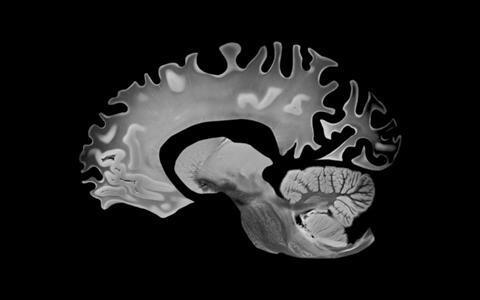

In March European Medicines Agency (EMA) advisors refused to back its approval, believing its benefits were not enough to outweigh the risk of potentially fatal events due to amyloid-related imaging abnormalities (ARIA), involving swelling and potential bleeding in the brain.